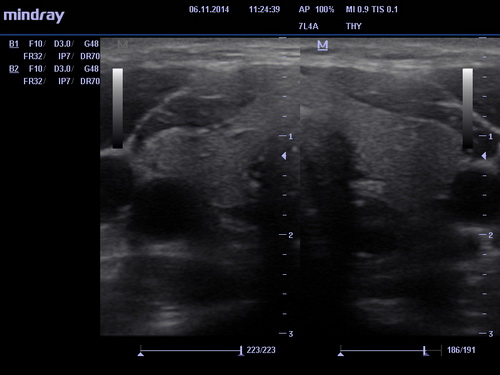

УЗИ щитовидной железы

УЗИ щитовидки полностью безопасная и безболезненная процедура. Врач, проводящий процедуру, предложит освободить шею и лечь на кушетку. Нанеся специальный гель на шею, он приступит к исследованиям. Осторожно двигая датчик вдоль шеи, стараясь лучше рассмотреть исследуемый орган, он зафиксирует все заметные изменения в нем. Небольшой датчик позволит прекрасно рассмотреть даже самые незначительные изменения.

Процедура занимает незначительное время. После нее нужно будет лишь убрать излишки геля с шеи. Квалифицированный специалист даст детальное письменное описание состояния исследованного органа.